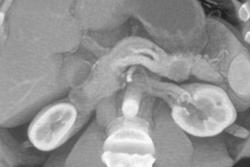

Gastric Cancer Invades the Pancreas